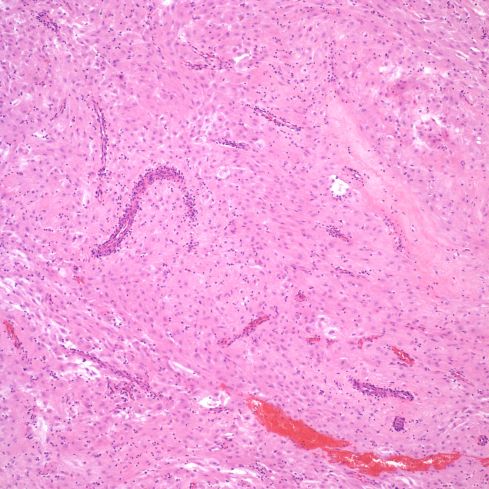

A perhaps understudied aspect of the spiral arteries in the basal decidua is their appearance when they underlie lesions of placental infarction, retroplacental hematoma, subchorionic thrombohematoma, and infarction hematoma. Those underlying infarctions may be distended with blood and thrombus (Figs 19-24).

Fig 19: The large, blood filled convoluted spiral artery at the base of the placenta shows lamina of fibrin. The infant was liveborn at 26 weeks of gestation, but was severely growth restricted. The mother had type 1 diabetes and chronic hypertension. The placenta had multiple infarctions. (H&E, 2x)

Fig 20: This view of the same spiral artery shows is proximity to a recent placental infarction. The presence of a thrombus in the vessel suggests that the infarction may have been caused by this very superficial thrombus, but there is no obvious clue as to how it formed. (H&E, 2x)